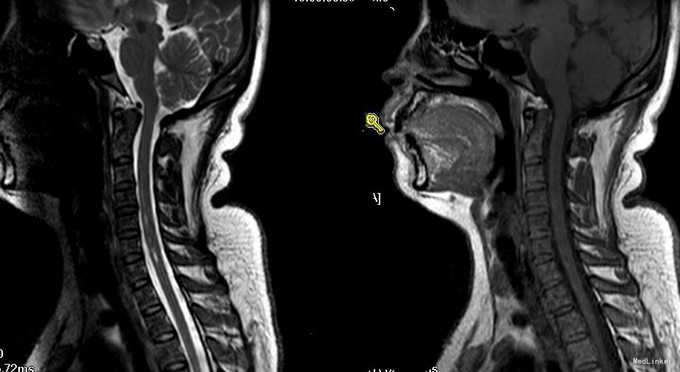

患者33岁,头晕、恶心呕吐10小时来诊。 患者孕35周,平日体检,进食正常,妊娠过程顺利。入院前10小时,无明显诱因出现头晕、恶心呕吐及走路不稳,急诊来我院产科,产科考虑与妊娠状态不服,请神经内科会诊,遂予完善颅脑MRI检查,提示右侧小脑半球新发梗塞,转入我可进一步治疗。既往有颈部疼痛病史。

神经科查体:神清语明,步态平稳,查体合作,双瞳孔等大正圆,D=3.0mm,对光反射灵敏,双眼球各向运动充分,无眼震,无复视,额纹对称,双侧鼻唇沟对称,示齿口角不偏,伸舌居中,咽反射存在,转颈耸肩对称有力,四肢肌力Ⅴ级,肌张力正常,深感觉未见异常,右侧指鼻、轮替、跟膝胫试验略差,闭目难立征及走直线征阴性,BCR L++R++,PSR L++R++,Babinski征L-R-,颈软。余神经系统查体未见明显异常。 颅脑MRI检查,提示右侧小脑半球新发梗塞,颈椎MRI:颈3-4T2高信号。MRA提示双侧椎动脉狭窄